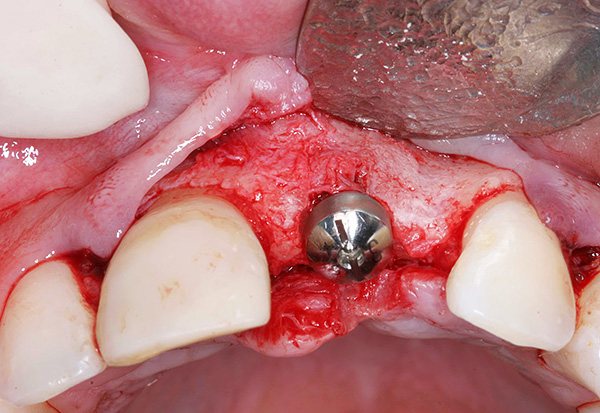

В настоящее время это осложнение имплантации встречается намного реже, чем бывало раньше. Прогресс произошел во многом благодаря возможности точно определить расстояние до полостных образований с помощью панорамных снимков и компьютерной томографии (КТ).

Для того чтобы свести риск этого осложнения практически к нулю, необходимо доверяться лишь опытному врачу с большим стажем работы, а в случае сомнений – проконсультироваться с другими имплантологами. В случае близкого расположения гайморовой пазухи и дна полости носа предварительно может быть проведено «наращивание» кости (синус-лифтинг), и тогда проблем не возникает.

На фото ниже показан пример наращивания костной ткани перед имплантацией зуба: